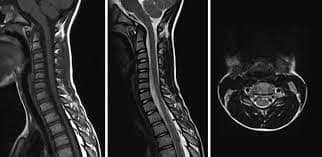

অ্যাকিউট ফ্ল্যাকসিড মাইলাইটিস বা এএফএম হলো একটি স্নায়বিক রোগ, যার ফলে, শরীর পক্ষাঘাতগ্রস্ত হয়ে পড়ে। ২০১৪ সাল থেকে প্রতি দুবছরে একবার করে অ্যাকিউট ফ্ল্যাকসিড মাইলাইটিস হানা দিয়েছে মার্কিন যুক্তরাষ্ট্রে।

এখনও পর্যন্ত এই রোগের কোনও প্রতিকার বা চিকিৎসা নেই। তাই রোগ নির্ণয় দ্রুত হলে, উপসর্গগুলির চিকিৎসা শুরু করা সম্ভব হবে। ফলে, থেরাপির মাধ্যমে আক্রান্তদের পক্ষাঘাতগ্রস্ত হাত ও পা পুনরায় সচল করতে তা সাহায্য করবে।